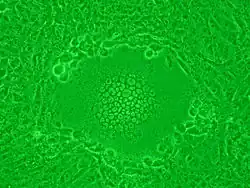

Zytopathogene Viren verursachen charakteristische morphologische Veränderungen der infizierten Zelle, die für bestimmte Virusarten typisch sind. Diese Veränderungen werden unter dem Oberbegriff cytopathischer Effekt (CPE) oder zytopathischer Effekt zusammengefasst.

Es werden verschiedene Ausprägungen des CPE unterschieden:

- Bildung mehrkerniger Riesenzellen (Synzytien), beruhend auf Zellverschmelzung (z. B. Paramyxoviridae)